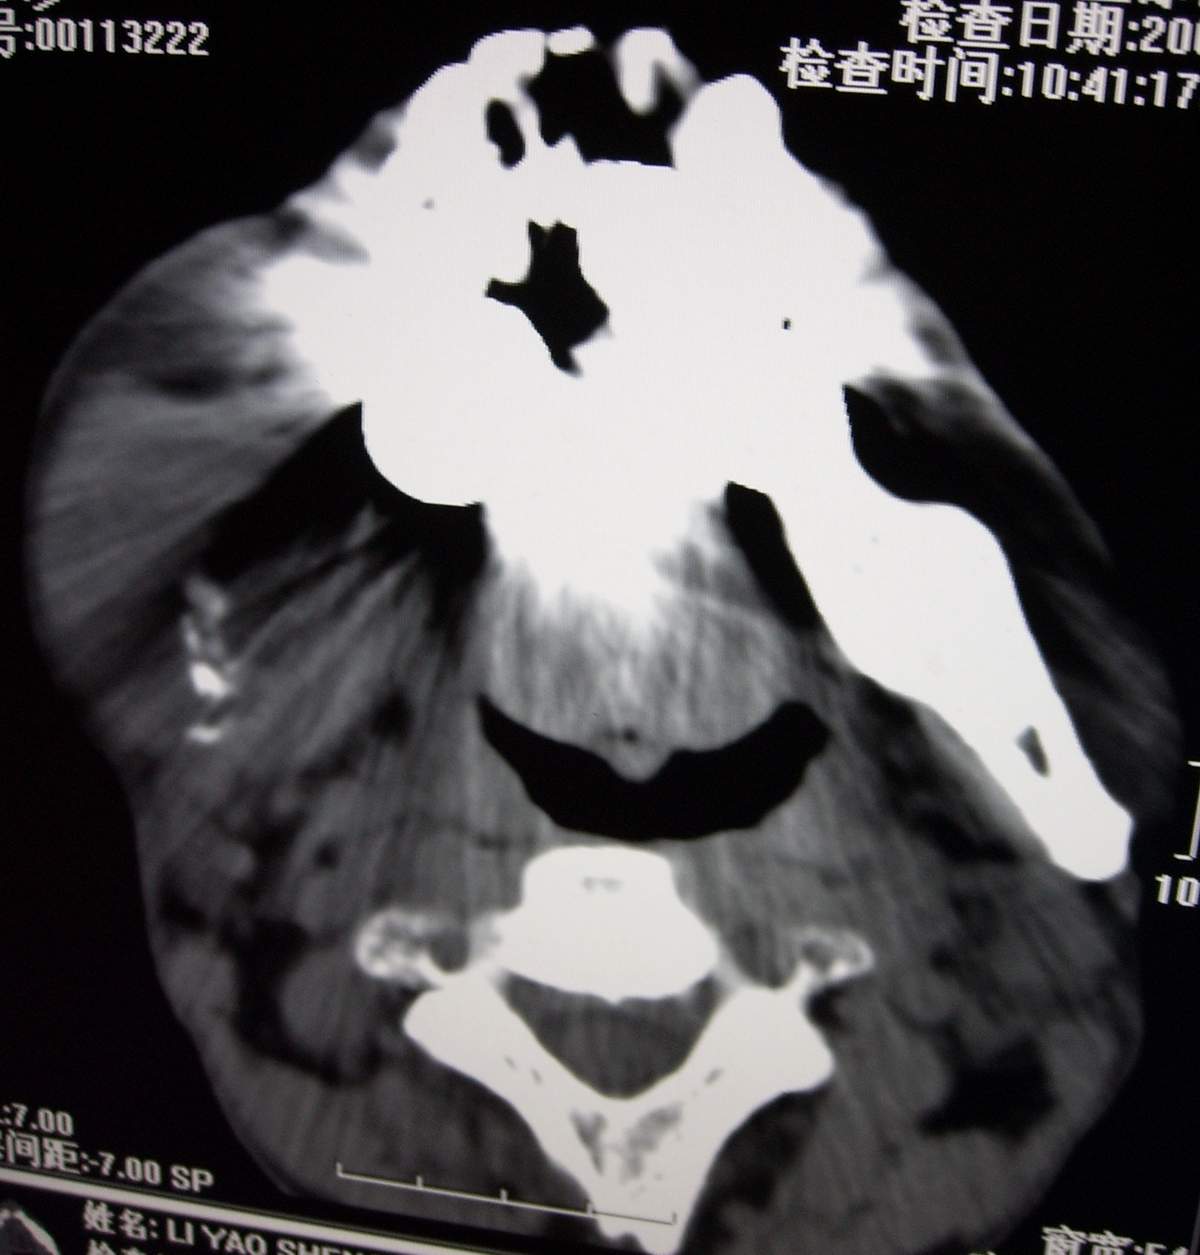

男,54岁,右下颌肿痛1月余。

右下颌骨溶骨性破坏,并见软组织形成。应考虑恶性肿瘤或转移瘤。

右侧下颌骨水平部及升支呈溶骨性破坏,无明显膨胀,周围见软组织肿块。

考虑:右侧下颌骨恶性肿瘤或转移瘤。

右下颌骨溶骨性破坏,代之以团块状软组织影,内有斑片状瘤骨,边缘骨质有少量骨膜反应,考虑:右下颌骨骨肉瘤。期待病理。